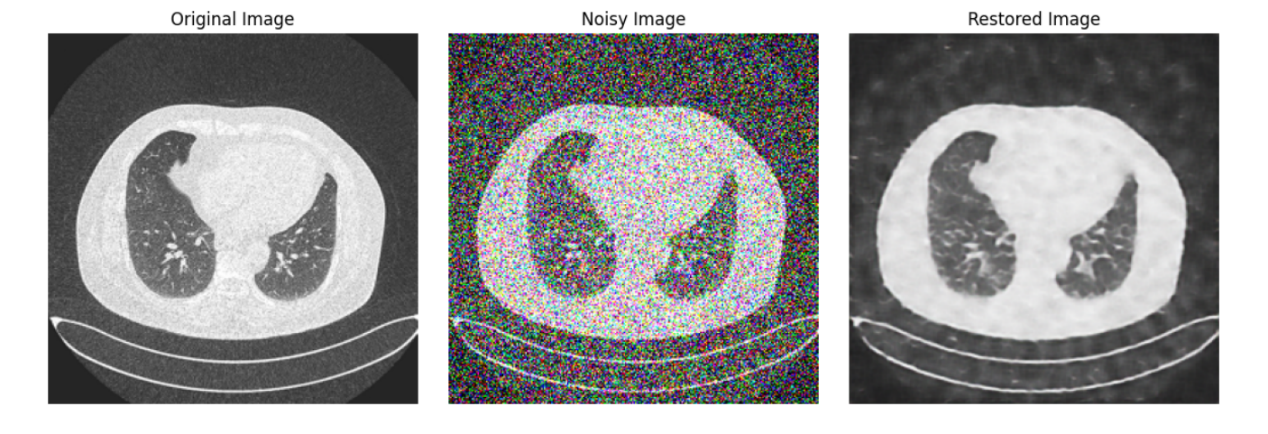

Image Restoration and Generation. Upon concluding training, the controlled diffusion model can be used to restore damaged medical images. This study introduced noisy images to the model, anticipating clear, noise-free medical image outputs.

Figure 3. The medical images generated by the diffusion model.

Through the structured delineation above, we've vividly showcased how to leverage the controlled diffusion model technique for medical image data handling, aimed at enhancing image quality and eliminating noise. This lays a robust foundation for subsequent research and applications in medical imagery. Figure 3 shows the medical image of lung cancer generated by the Diffusion model.

By observing the image generated by the diffusion model, it can be observed that it has more and better details, and it only uses 10 Epoch for training shown in Figure 5. It almost perfectly imitates the original image, although it has a huge flaw, that is the generation speed is very slow.

Diffusion Model: The diffusion model-generated images, depicted in Figure 3, showcased superior fidelity. These images retained a significant amount of the details seen in the original lung cancer CT scans, thereby demonstrating its ability to generate more clinically useful images.

Diffusion Model: While the diffusion model required a mere 10 epochs, its generative process was notably slower. Although this model delivers superior image quality, its prolonged generation time might be a bottleneck in certain applications.